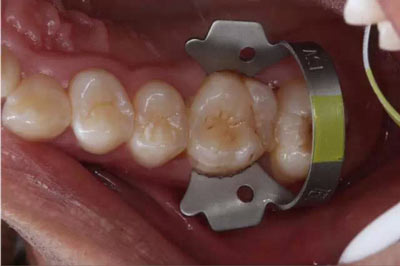

第三步:用橡皮障夾鉗撐開橡皮障夾,口內(nèi)就位后,再把橡皮障夾兩側(cè)翼的橡皮布用牙齦剝離器推向齦端

三、臨床應(yīng)用小貼士: